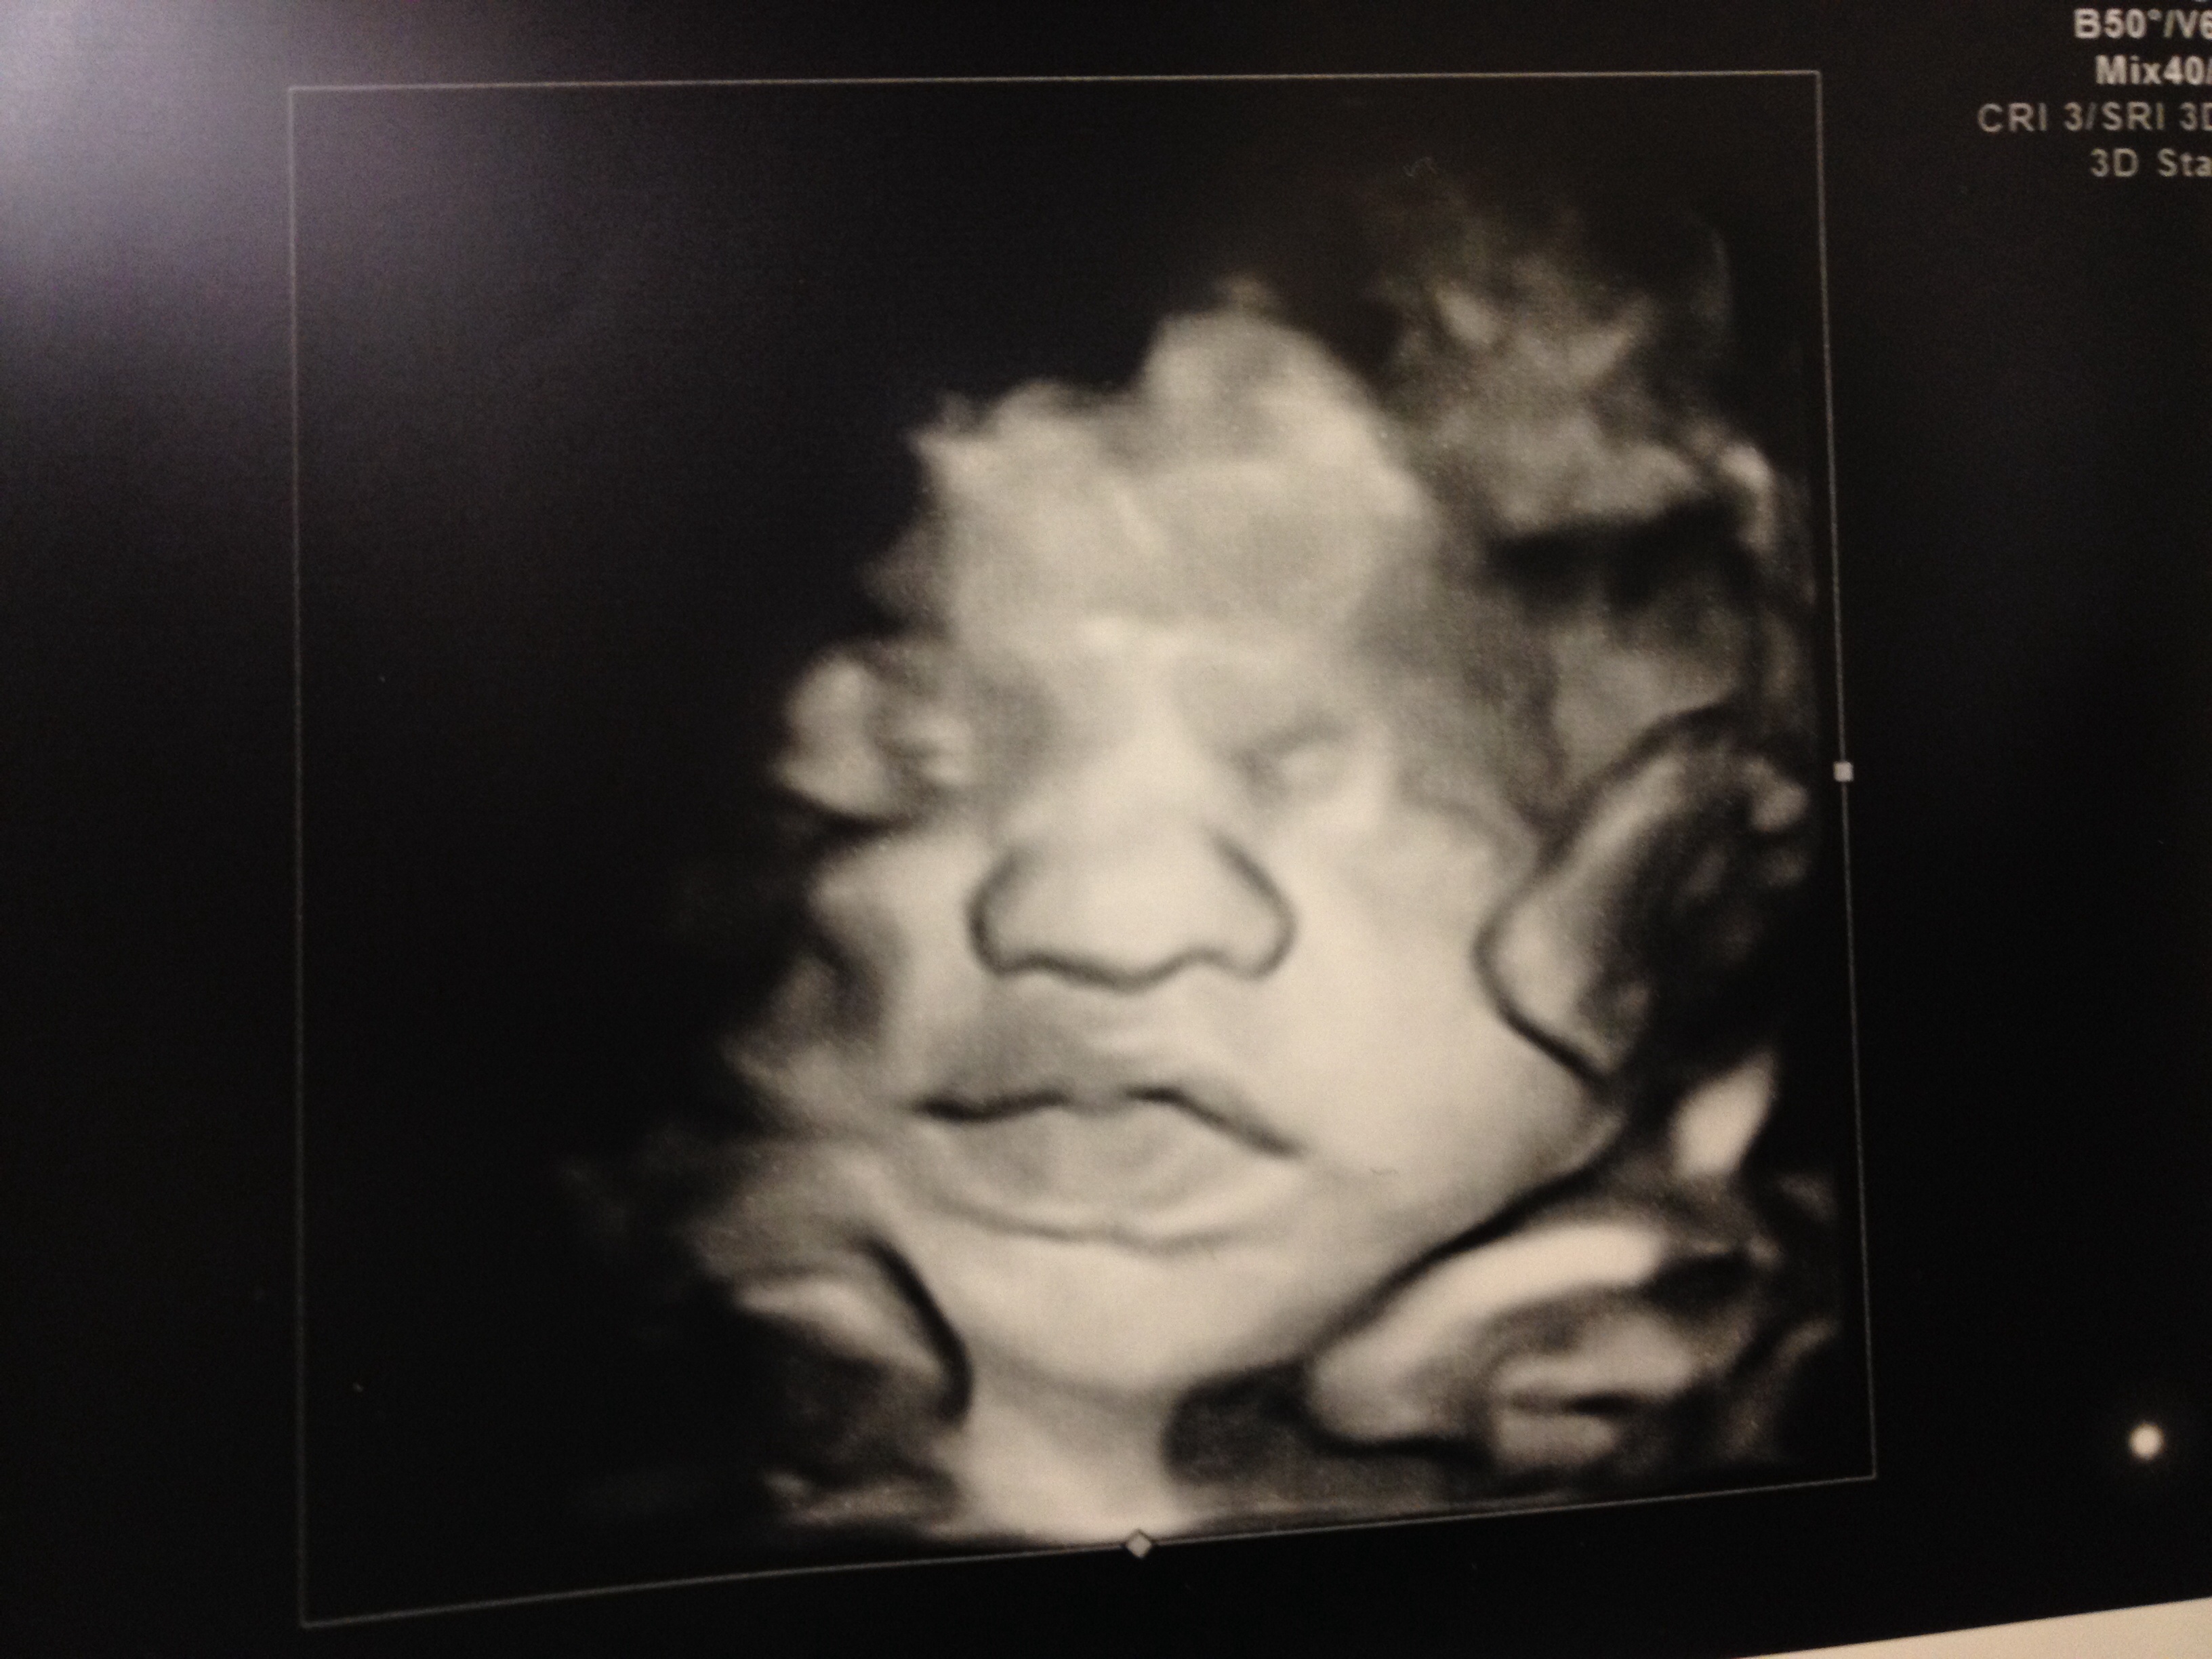

Warning: 3D US pics! Lol. If you don't like em, click away now!

We had ours done today! Here's LO!

Funny story: my mom wanted to know why he was bumpy. I've explained this before to her, I think she thinks I'm having a bumpy baby.